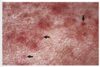

Gross appearance of insect bite hypersensitivity

Often includes papules